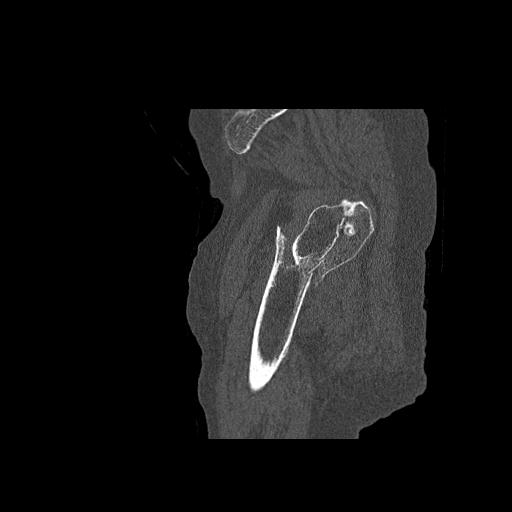

56476 8/28 4R 1/21 2R 左足関節 デジカメ写真 72歳女性 右足関節AS